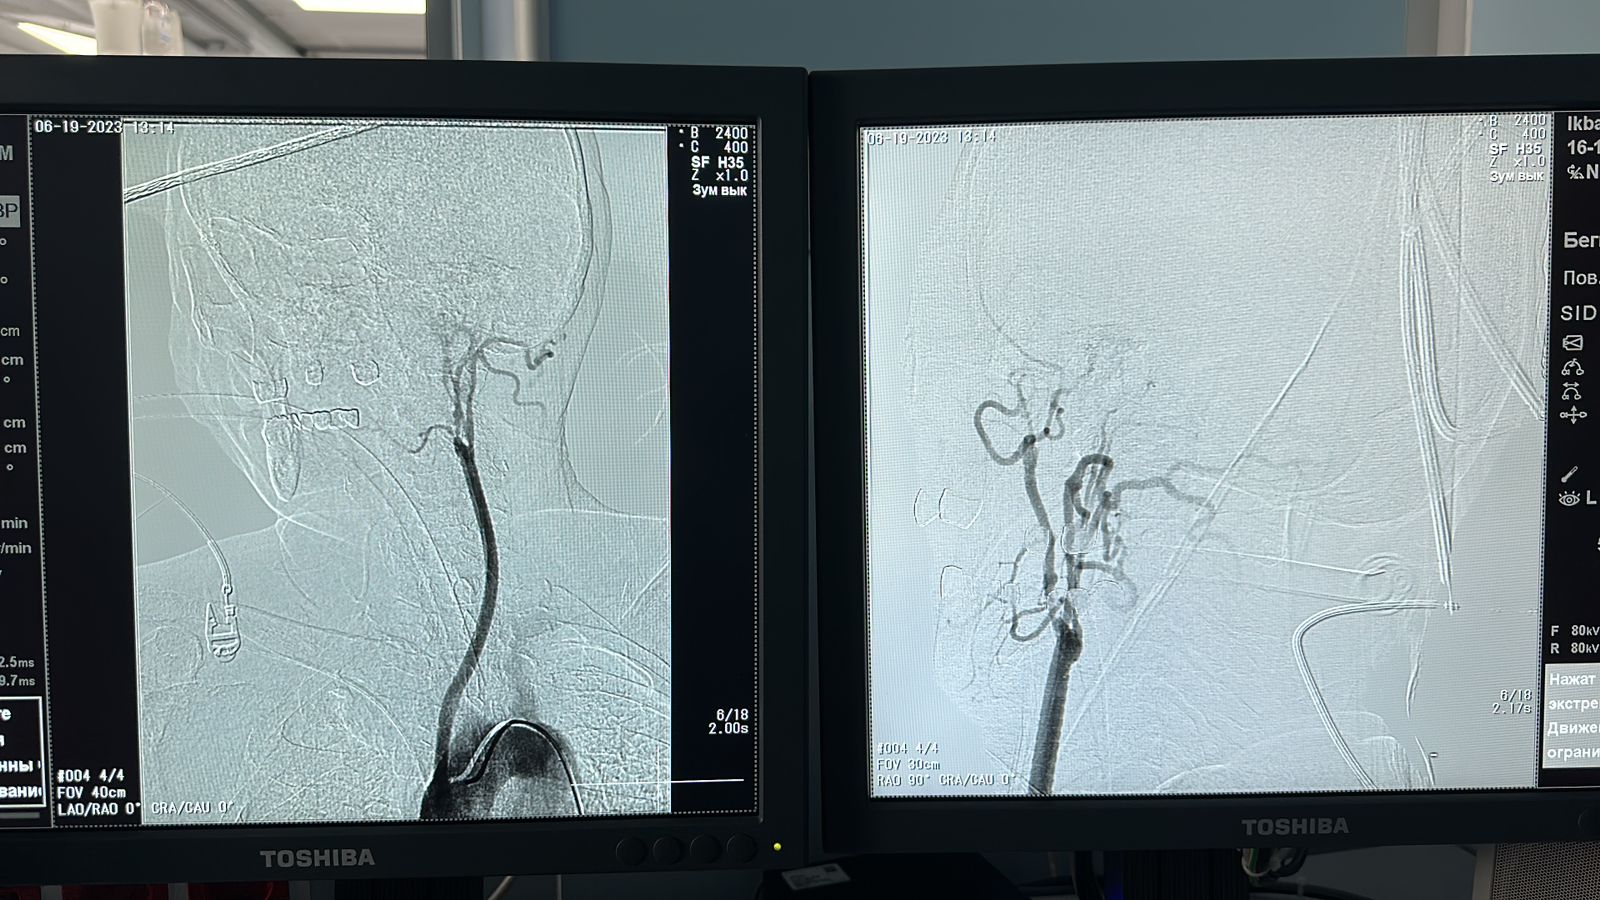

– Bizge kelgen naýqastyń mıǵa baratyn eń negizgi eki jaqty ishki uıqy arterııalary, sonymen qosa omyrtqalyq arterııalary tolyq bitelip qalǵan bolatyn. Bastaǵy qantamyrlar buǵana arterııasynan shyǵatyn moıyndyq baılam tamyrynan qorektenip júrgen. Bul jerde kardıohırýgterdiń de aralasýy qajet edi. Sebebi júrekten shyǵatyn aorta tamyryna blog ornatý josparlandy. Sheteldik áriptesterdiń tájirıbesin zertteı kele jáne ózimizdegi zamanaýı tehnıkalyq múmkindikti paıdalana otyryp Kardıohırýrgııa bólimshesiniń meńgerýshisi Álibek Toıbaevpen birlese alǵash ret «Takaıasý» dıagnozyna operasııa jasap shyqtyq. «Kelisip pishken ton kelte bolmas» degendeı, qazir naýqastyń jaǵdaıy jaqsy, bastaǵy aýyrsynýlar tarqaǵan, – deıdi neırohırýrg dáriger Islambek Musabekov.

Tamyrlardyń bitelýi jıi kezdesetin aýrý bolǵanymen, ony emdeý kúrdeli prosess. Sátti jasalǵan operasııadan keıin neırohırýrg pen kardıohırýrg dárigerler kelesi naýqastarǵa kómektesýge daıyn.